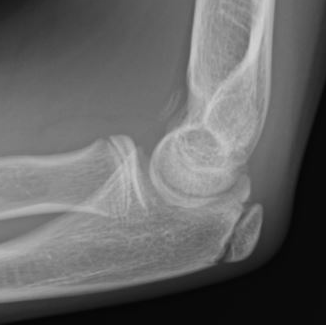

Multiple elbow loose bodies

lblblb